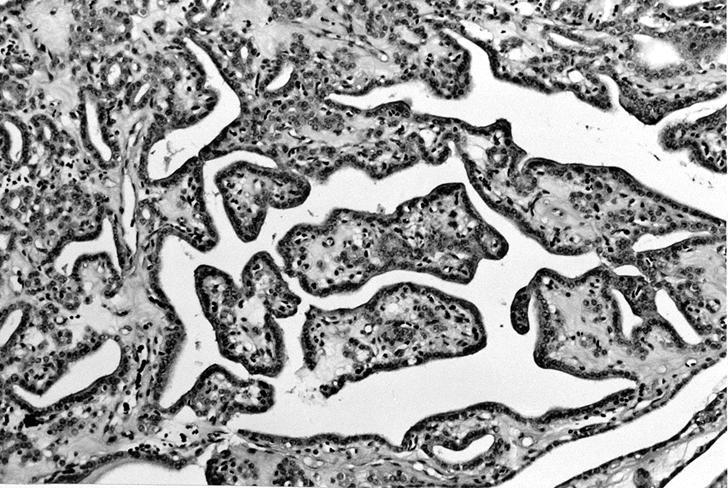

Microscopic (histologic) images

Contributed by Shipra Agarwal, M.D., Andrey Bychkov, M.D., Ph.D., Mark R. Wick, M.D., Asmaa Gaber Abdou, M.D. and AFIP

Patterns:

Microscopic (histologic) description

- Architecturally and cytologically different from surrounding gland

- Compression signs in surrounding thyroid tissue

- Encapsulated; thin or moderately thick capsule

- Architectural patterns (can be seen in any combination)

- Normofollicular (simple): size similar to normal thyroid follicles

- Microfollicular (fetal): smaller follicles, small amount of intraluminal colloid

- Macrofollicular (colloid): large follicles, flattened epithelium, abundant colloid

- Solid / trabecular (embryonal): minimal or no colloid

- Focal papillary pattern, occasionally; especially in hyperfunctioning adenoma and follicular adenoma with papillary hyperplasia

- Cuboidal to low columnar cells

- Small round nuclei, smooth nuclear boundary, uniformly hyperchromatic or euchromatic, dense chromatin, absent nuclear features of papillary thyroid carcinoma, nuclear score 0 or 1 (JAMA Oncol 2016;2:1023)

- Inconspicuous nucleoli

- Rarely, lipid filled vacuoles in cytoplasm

- Mitoses are uncommon

- Scant stroma

- Secondary changes: fibrosis, hyalinization, hemorrhage, hemosiderin deposition, edema, cystic degeneration, calcification, osseous or cartilaginous metaplasia

- Variants

- Hyperfunctioning adenoma (Plummer adenoma): tall columnar epithelium, papillary infoldings, vacuolated cytoplasm, watery colloid showing scalloping

- Follicular adenoma with papillary hyperplasia: cystically dilated follicles, intraluminal papillae